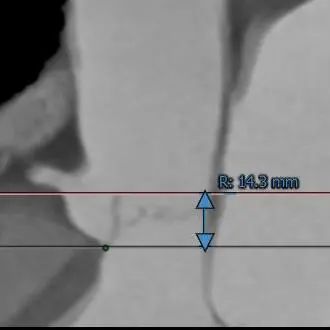

RCA Height:14.3 mm